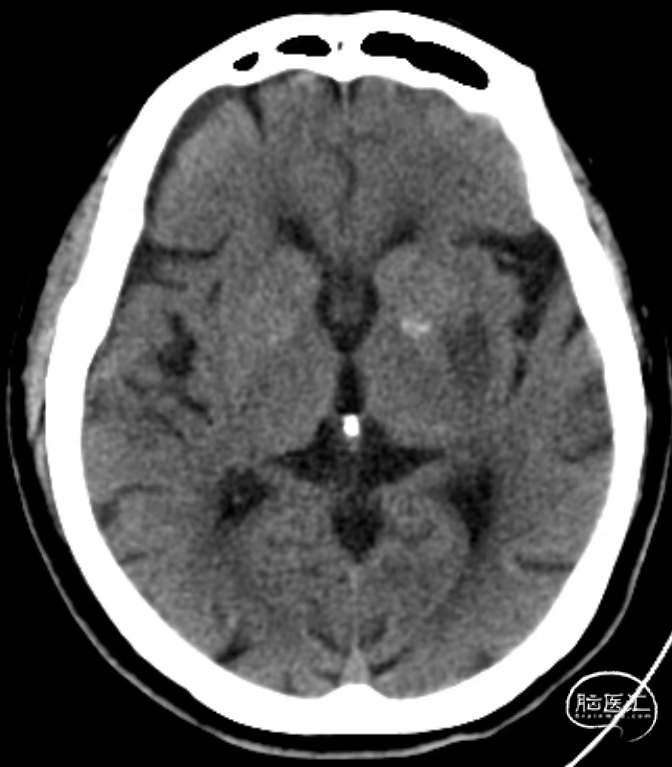

入院时CT:ASPECTS 10分。

术前MRI